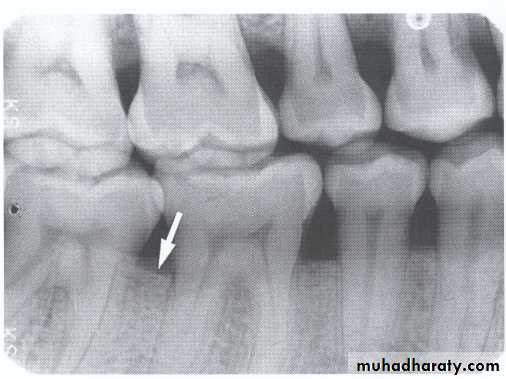

A-Calculus:

It is a stone-like concretion that forms on the crown & roots of the teeth due to the calcification of bacterial plaque.

Its appear as radiopaque on the dental radiograph.

its either pointed or irregular radiopaque projection extending from the proximal root surface.

Calculus may be seen as a ring-like radiopacity encircling the cervical portion of the tooth.